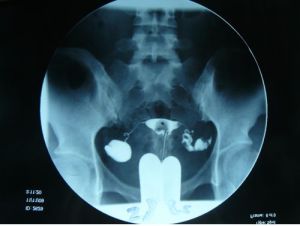

檢查

盆腔積水檢查對識別來自輸卵管、卵巢及腸管粘連形成的包塊或膿腫有85%的準確性。一般用來診斷較為嚴重的盆腔炎。